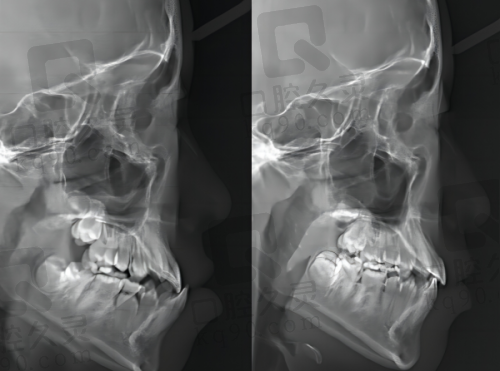

在了解患者情况后,门诊部会为患者量身定制个性化的口腔诊疗方案。比如,对于牙齿矫正患者,如果是轻度的牙齿不齐,可能会推荐相对简单、经济的矫正方式;而对于较为复杂的牙齿畸形,则会制定更全方面、针对性更强的矫正方案。这种个性化的诊疗方案充分考虑了患者的个体差异,能够提高治疗的成效和效率。

在牙齿矫正方面,门诊部提供了多种矫正方式供患者选择。不同的矫正方式有不同的特点和适用人群。例如,钢丝牙套价格相对较低,矫正周期短且适应范围广;隐形牙套美观舒适不磨嘴,清洁起来比较方便,适合对美观度要求较高的患者。